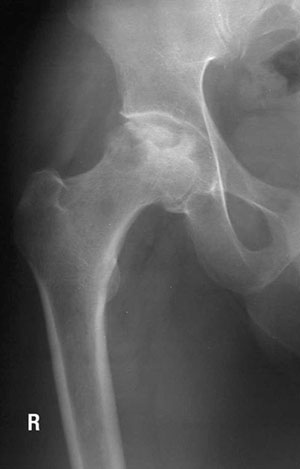

An x-ray showing a damaged hip bone.

Bone fractures and osteonecrosis have been associated with exposure to common leukemia therapy drugs such as corticosteroids and methotrexate. Bone toxicity is an extremely debilitating condition that often leads to lifelong pain, shortened limbs, has difficult recovery and may lead to impaired quality of life.  Our team wanted to explore if there are any genetic variants that make some children more at risk for bone damage including fractures and osteonecrosis.

Our findings are significant, as we found that 20 per cent of the 615 study’s participants had a genetic variant in the gene for thymidylate synthase that was associated with increased risk of bone fractures and osteonecrosis. We also found that kids who were diagnosed with leukemia at age 10 or older were more at risk for bone fractures, while those who were younger than 10 years old when they had leukemia were more at risk for osteonecrosis. This is a novel observation.